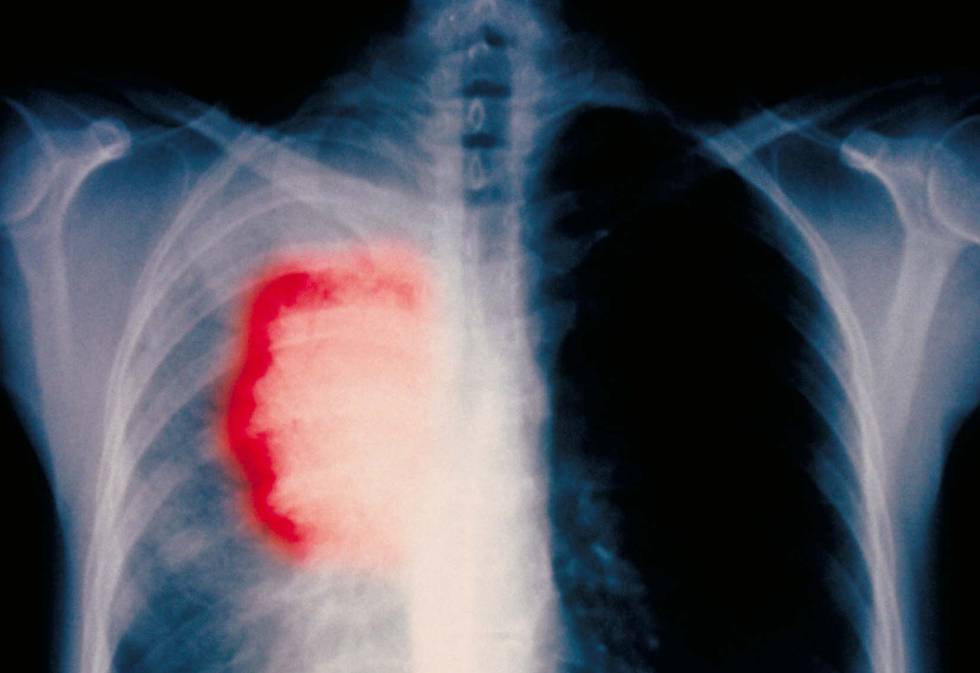

Personas con el tipo de cáncer de pulmón más frecuente, que hasta hace unas décadas no sobrevivían más de dos años luego del diagnóstico, tienen en la actualidad una sobrevida cada vez mayor gracias a la inmunoterapia, que logra eliminar los signos de la enfermedad en el 80% de los casos, afirmó el oncólogo español Ignacio Gil Bazo.

El cáncer de pulmón es el tumor maligno más frecuente a nivel mundial y uno de los más letales, especialmente si se diagnostica tarde.